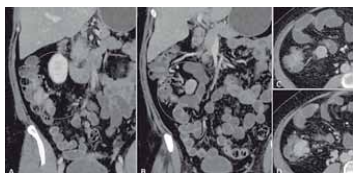

A imagem a seguir apresenta lesão expansiva hipervascular no íleo terminal: linfonodomegalia mesentérica

regional. Anatomopatológico: carcinoide de íleo terminal

com comprometimento linfonodal:

Aquisição foi feita pelo método de